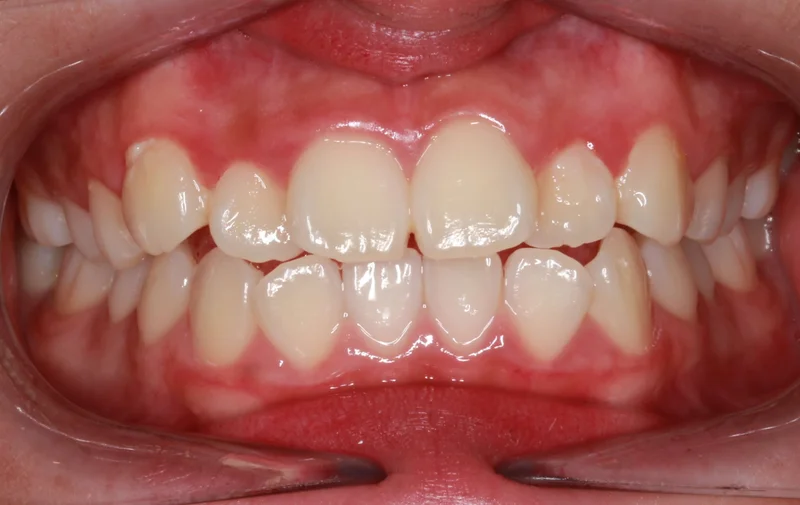

Center Bite - Before Treatment

Before